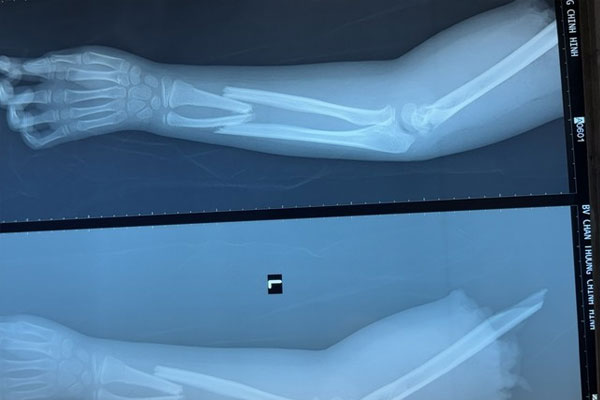

Người nhà đã bảo quản cánh tay trong thùng đá và chuyển cùng bệnh nhi đi cấp cứu. Tại Bệnh viện Chấn thương Chỉnh hình, các bác sĩ đã kiểm tra hình ảnh và phát hiện, ngoài tình trạng bị đứt lìa, cánh tay bệnh nhi còn bị gãy ở cẳng tay, vị trí đứt lìa dập nát phức tạp.